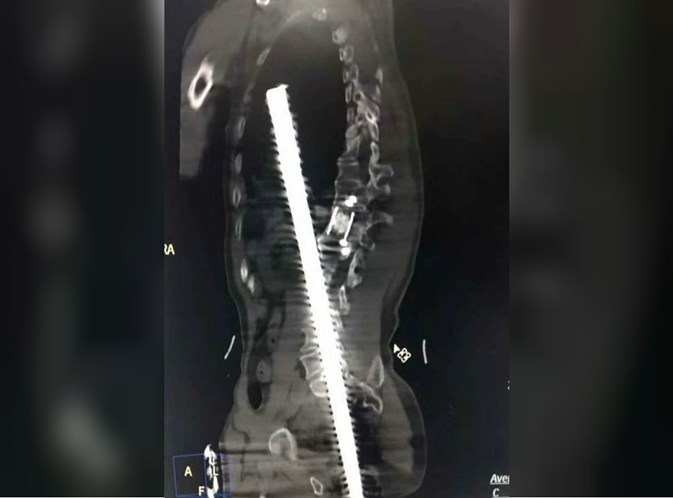

Os exames mostram a gravidade das lesões, a barra parou no tórax do homem. Foi realizada uma cirurgia de emergência que durou 6 horas para remover o objeto, que por milagre, não atingiu nenhum órgão vital.